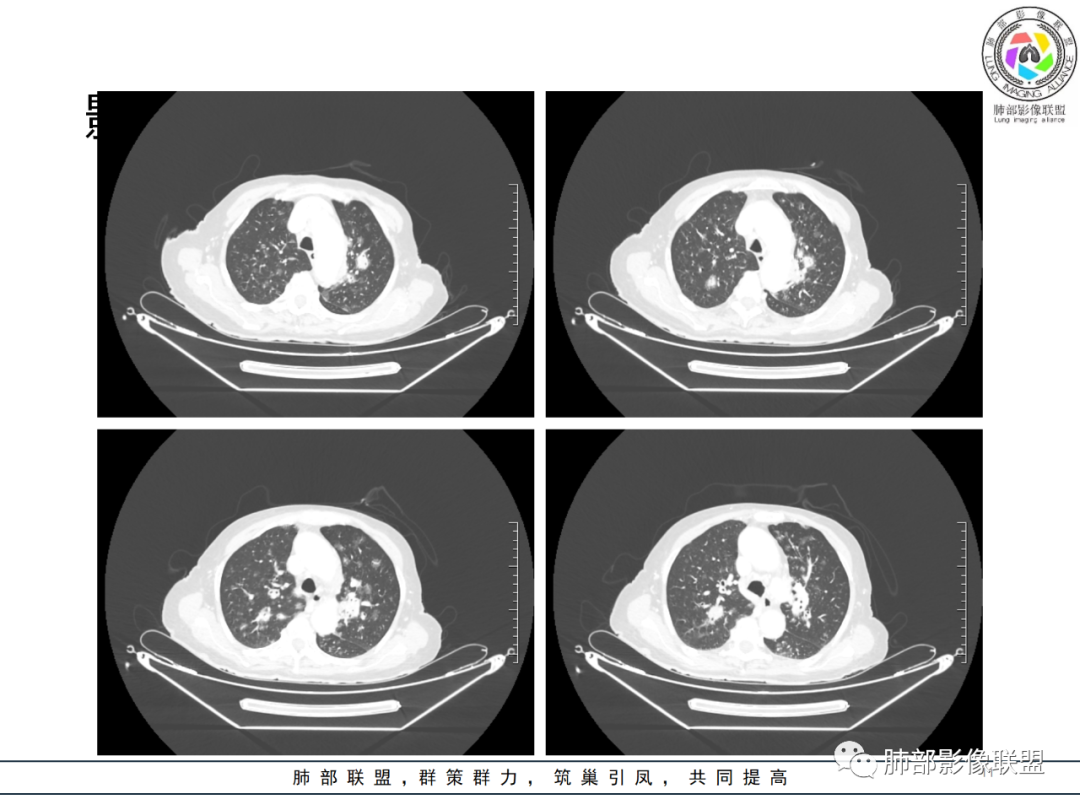

影像资料

82岁女性,反复发热入院,查外周血白细胞升高,抗生素治疗可缓解,支持细菌感染性发热,结合肾脏肿瘤,考虑泌尿系感染发热;CT提示双肺多发毛玻璃影,右下肺多发大结节影,3月复查,双上肺毛玻璃影/混合毛玻璃影增多,部分呈点晕征,右下肺多发肿块,可见支气管穿行,双下肺中轴间质增厚,左肾占位,肺部病变考虑:1.淋巴瘤 2.肾癌肺转移

老年女性,近期反复的发热,胸部CT基础尚可,心影增大,双肺下叶血管束增粗,3个月后复查 提示双肺多发磨玻璃密度影,并有磨玻璃影内部血管的穿行,双肺下叶血管束的增粗,纵隔窗下未见纵隔肿大的淋巴结,血管通畅,未见血管壁的增厚,左肾肿瘤?肺内病变不符合支气管束分布,暂不考虑吸入性,考虑淋巴管或血管源性病变。总体考虑非感染性病变可能性大,血管炎?淋巴瘤?

老年女性患者,发热就医,两肺片状影,沿支气管血管束分布,炎性指标升高,糖尿病基础,首诊考虑肺部感染合乎情理,这也是常见病!事实上,患者抗感染治疗好转出院。

三月后患者再次因发热就医,病灶在“原址”基础之上范围扩大,病灶增多(而非此起彼伏),就有些不同寻常,仅如此高龄,如此大范围感染,持续三月之久?太难以想象。